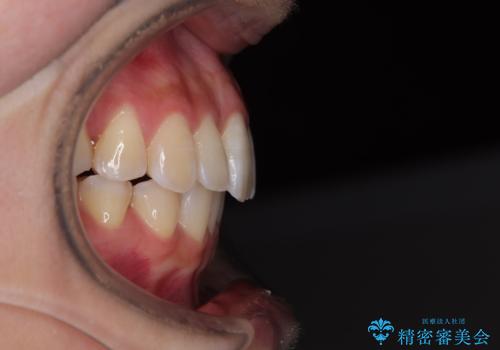

1年弱で治療方針を変更したため、治療期間は長くなりましたが、スペースは無事に閉じ、咬合の違和感なく仕上げることができました。

ただし、両方の臼歯部は理想的な咬合とは言えないため、咬合による歯の外傷を防ぐため、就寝時にはマウスピースを継続使用するようお願いしております。